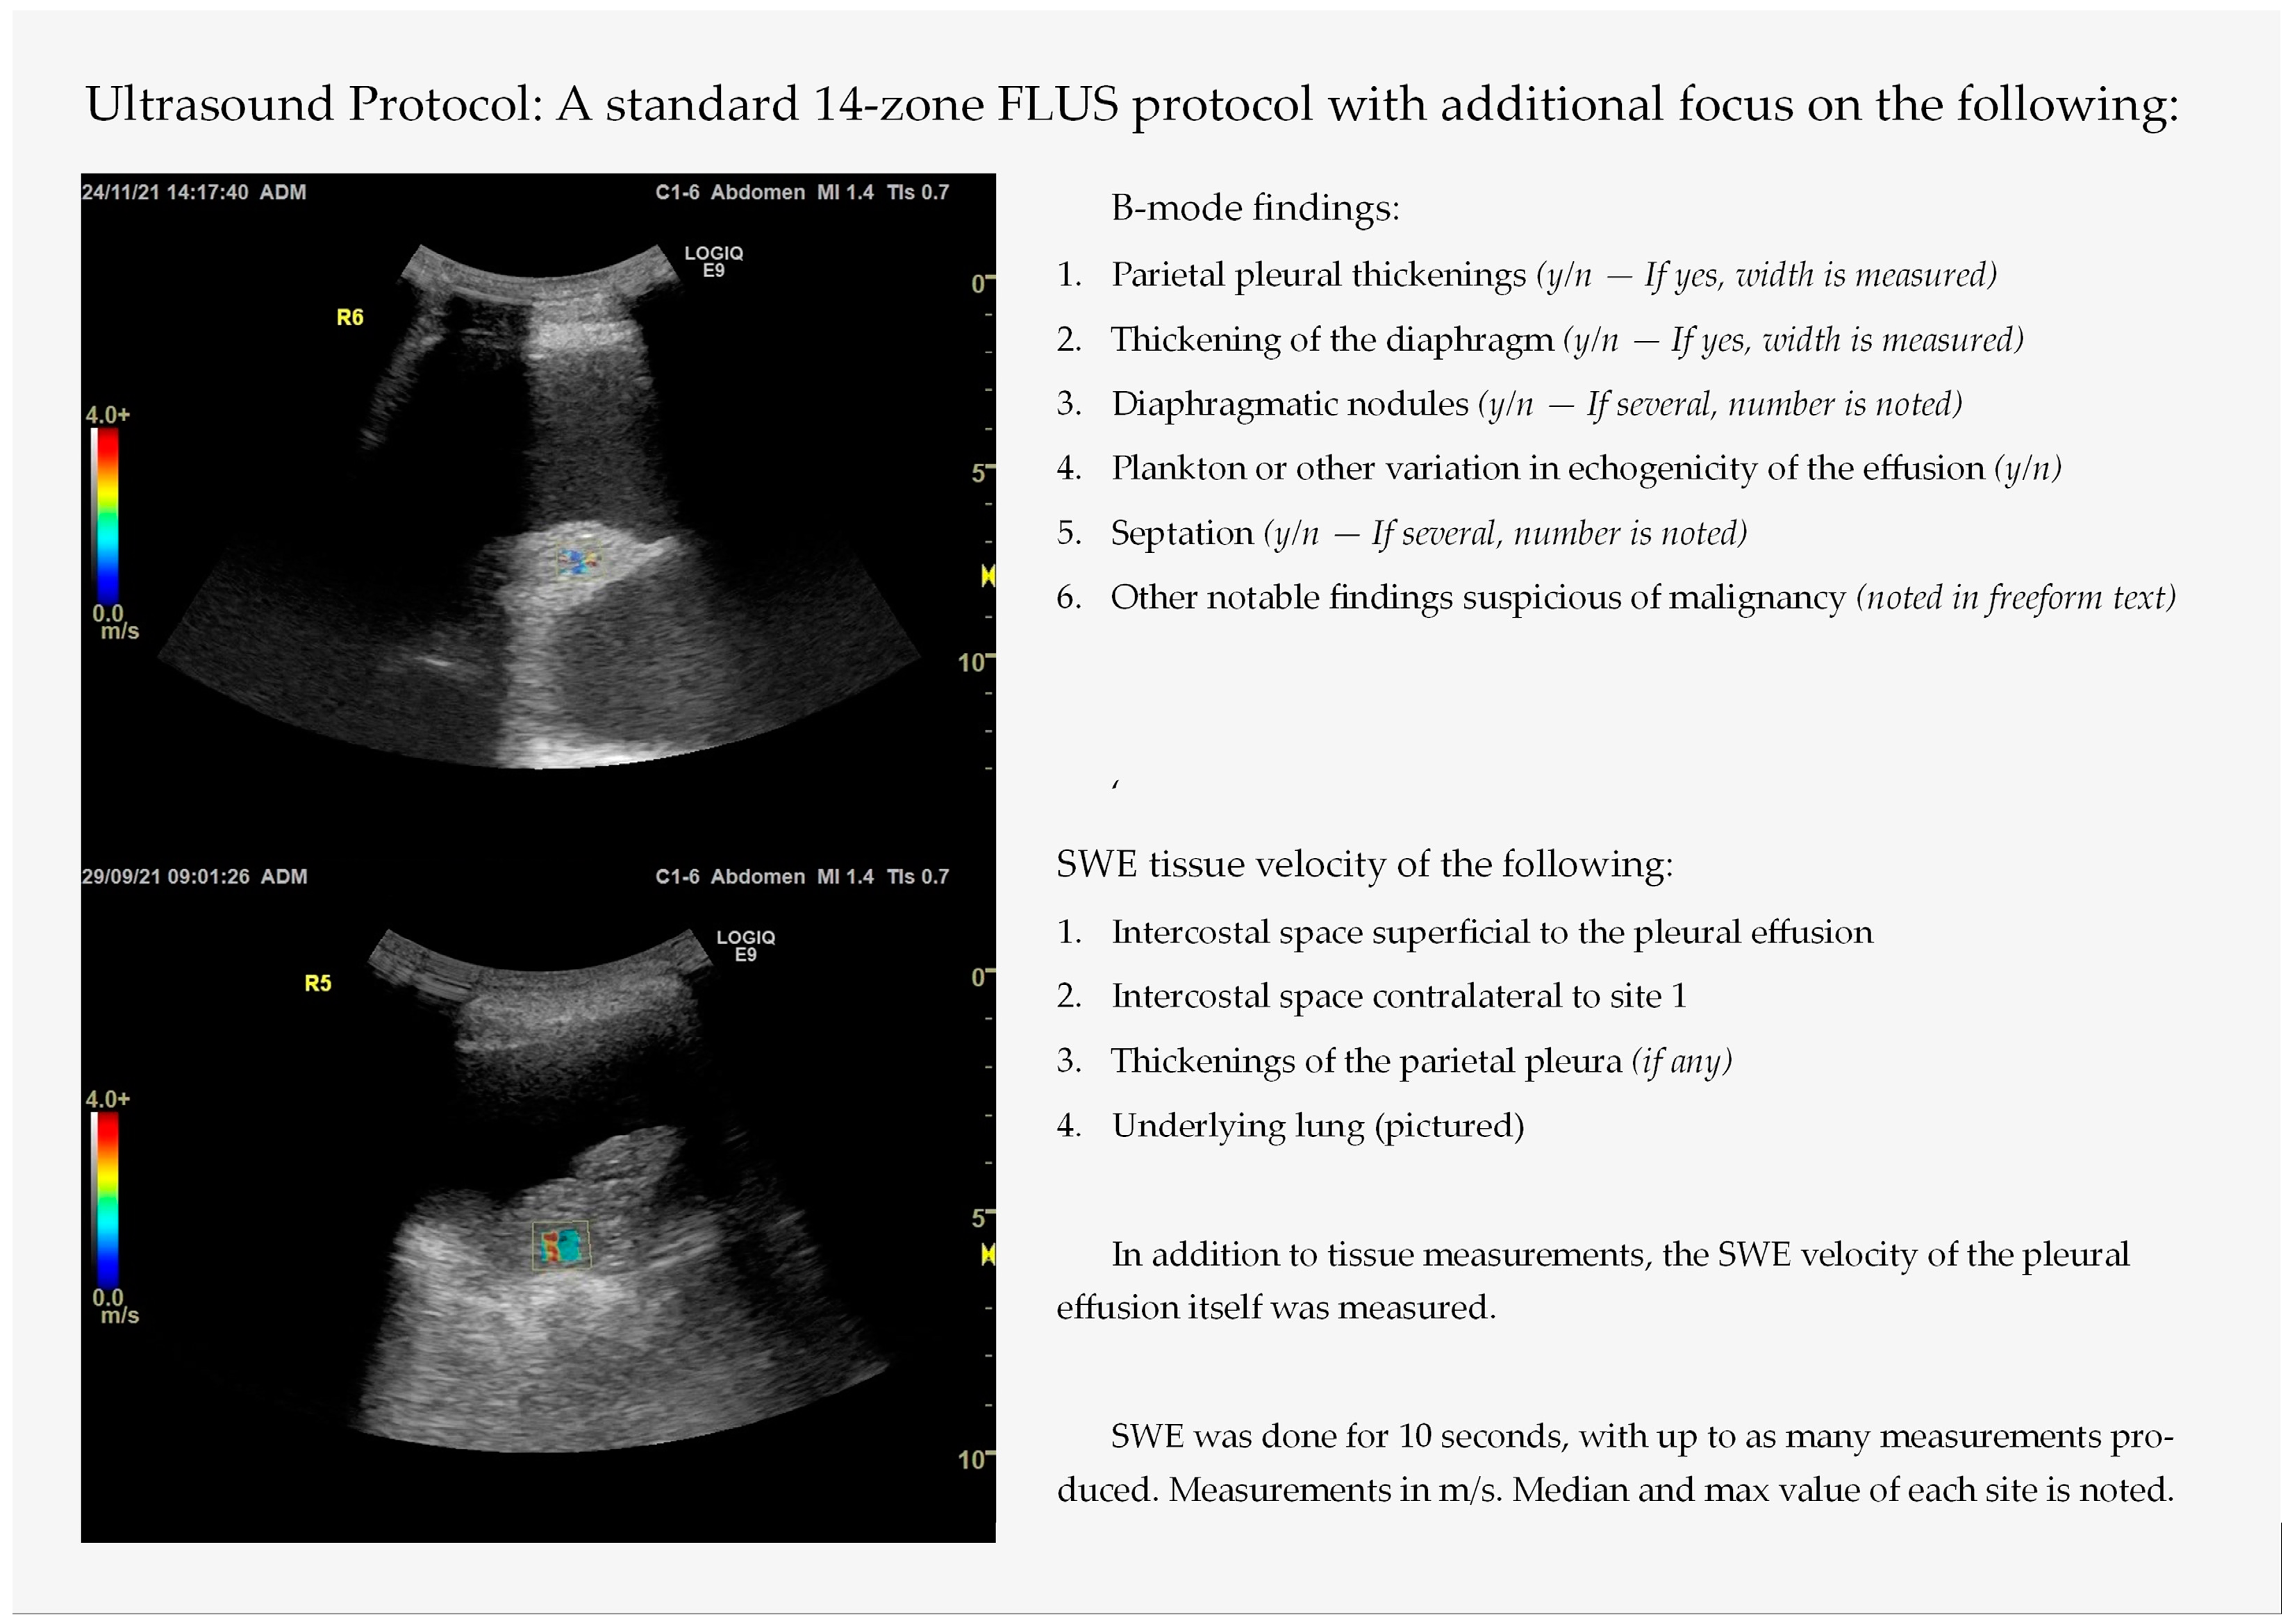

2.2. Thoracic Ultrasound with Integrated Elastography—Index Test

Focused Lung Ultrasound with Integrated Elastography—Procedure